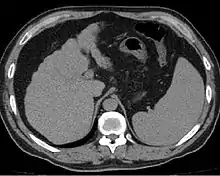

Other scans include CT of the abdomen and MRI.[36] A CT scan is non-invasive and may be helpful in the diagnosis.[36] Compared to the ultrasound, CT scans tend to be more expensive. MRI provides excellent evaluation; however, is a high expense.[36]